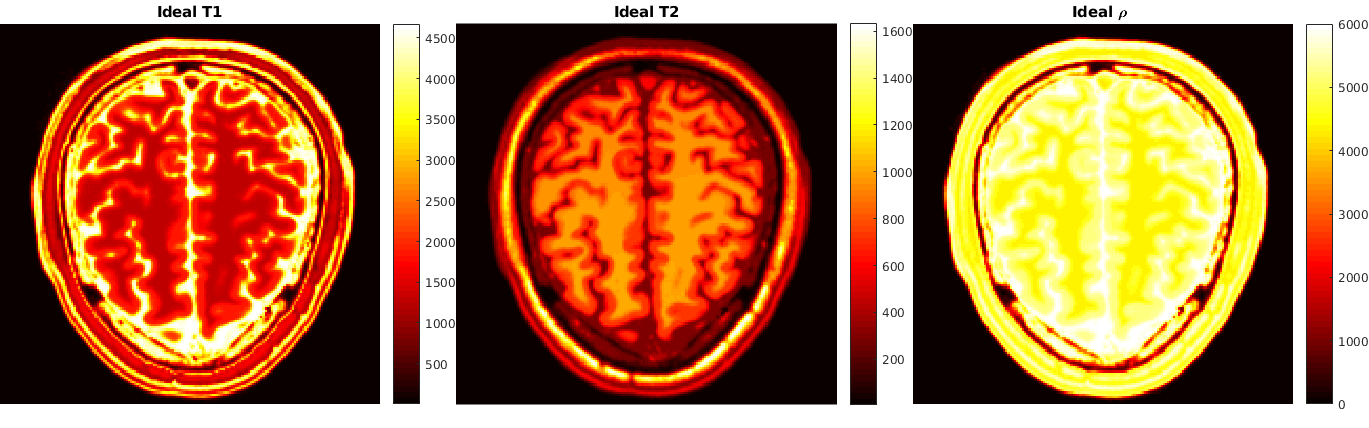

The second example comes from quantitative magnetic resonance imaging - qMRI. In this context, one integrates a mathematical model of the acquisition physics (the Bloch equations [16]) into the associated image reconstruction task in order to relate qualitative information (such as the net magnetization y=ρm𝑦𝜌𝑚y=\rho m) with objective, tissue dependent quantitative information (such as T1subscript𝑇1T_{1} and T2subscript𝑇2T_{2}, the longitudinal and the transverse relaxation times, respectively, or the proton spin density ρ𝜌\rho). This model is then used to obtain quantitative reconstructions from subsampled measurement data g𝑔g in k-space by a variational approach. The provision of such quantitative reconstructions is highly important, e.g., for subsequent automated image classification procedures to identify tissue anomalies. Moreover, in [16] it is demonstrated that such an integrated physics-based approach is superior to the state-of-the-art technique of magnetic resonance fingerprinting (MRF) [32] and its improved variants [14, 34]. Specifically in MRI, acquisition data are obtained at different pre-specified times (read-out times) t1,,tLsubscript𝑡1subscript𝑡𝐿t_{1},\ldots,t_{L}, during which the magnetization of the matter is excited through the control of a time dependent external magnetic field B𝐵B. Given u=(T1,T2,ρ)𝑢subscript𝑇1subscript𝑇2𝜌u=(T_{1},T_{2},\rho), the magnetization time vector at t1,tLsubscript𝑡1subscript𝑡𝐿t_{1},\ldots t_{L} is then given by y=Π(u)𝑦Π𝑢y=\Pi(u), where ΠΠ\Pi denotes the solution map associated with a discrete version of the Bloch equations. Crucial to this approach is the fact that, at least for specific variations of the external magnetic field B𝐵B, explicit formulas for the solution map of the Bloch equations are available. For instance, in [14] and [16] Inversion Recovery balanced Steady-State Free Precession (IR-bSSFP) [41] is used which involves certain flip angle sequence patterns that characterize the external magnetic field B𝐵B. These flip angle patterns allow for a simple approximation of the solutions of the Bloch equations at the read-out times through a recurrence formula. However, in general, it is quite typical that for more complicated external magnetic fields one does not have at hand explicit representations for the Bloch solution map. More generally, for most nonlinear differential equations (including those relevant in image reconstruction tasks) explicit solution maps might be too complicated to obtain. However, one may employ numerical methods to approximate their solutions (yi)i=1nDsuperscriptsubscriptsubscript𝑦𝑖𝑖1subscript𝑛𝐷(y_{i})_{i=1}^{{n_{D}}} given a specific (coarse) selection of parameters (ui)i=1nDsuperscriptsubscriptsubscript𝑢𝑖𝑖1subscript𝑛𝐷(u_{i})_{i=1}^{{n_{D}}} within a certain range. This generates a data set D𝐷D which is then employed in a learning procedure to generate an ANN based approximation Π𝒩subscriptΠ𝒩\Pi_{\mathcal{N}} of ΠΠ\Pi. This gives rise to Q𝒩:=AΠ𝒩assignsubscript𝑄𝒩𝐴subscriptΠ𝒩Q_{\mathcal{N}}:=A\Pi_{\mathcal{N}} in (1.2) and requires an associated analytical as well as numerical treatment of the (reduced) minimization problem.